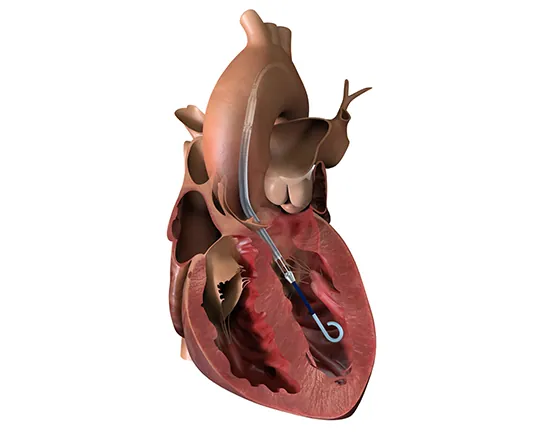

Ablación septal: cuándo se plantea y en qué consiste

Una mirada detallada a este procedimiento cardiológico y sus indicaciones